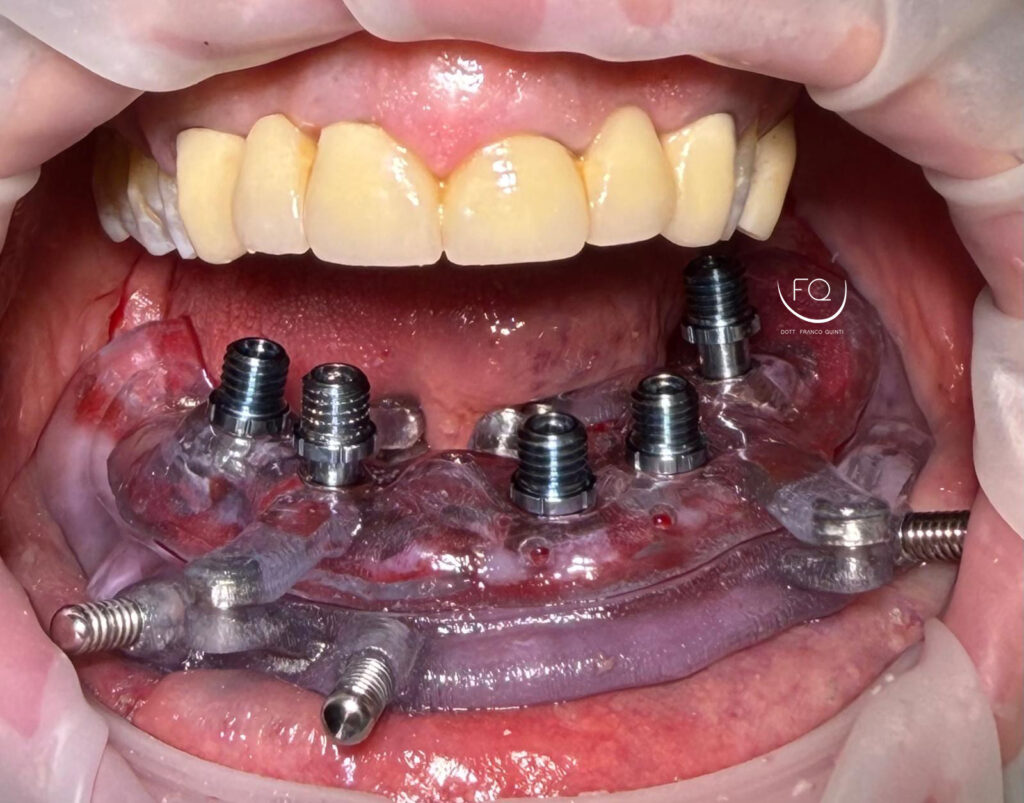

Oggi vi presento un caso di chirurgia computer guidata eseguito con Dima scomponibile.

Dall’immagine iniziale è possibile apprezzare l’estrusione del gruppo incisivo inferiore il quale è stato corretta con la protesi provvisoria a carico immediato stampata in 3D.